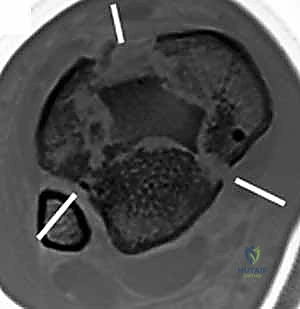

22.

Cole et al3 mapped 38 consecutive AO/OTA 43-C3 (complex articular) plafond fractures with CT scans and found that all plafond fractures in this category exited the tibiofibular joint laterally and at two separate locations medially to create a coronally oriented Y pattern with three major fragments ( FIG 2A). There were also varying amounts of articular comminution anterolaterally or anteromedially (FIG 2B).

--- A B ### FIG 2 • A,B. CT images from 43-C3 plafond injuries demonstrating typical fracture patterns with anterolateral, medial malleolus, and posteromedial fragments. Variable amounts of central or anterocentral articular impaction and comminution are commonly seen.